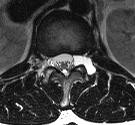

[画像診断]子宮筋腫変異型およびlipoleiomyomaについて 2010-07-07